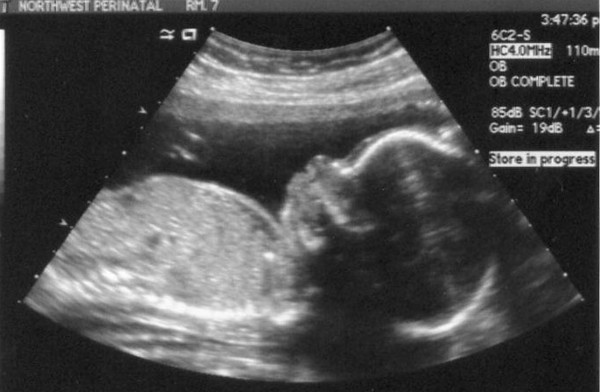

This was our favorite picture from today - a decent view of Junior's face. Doesn't it kind of look like he is grinning?

Junior's profile.